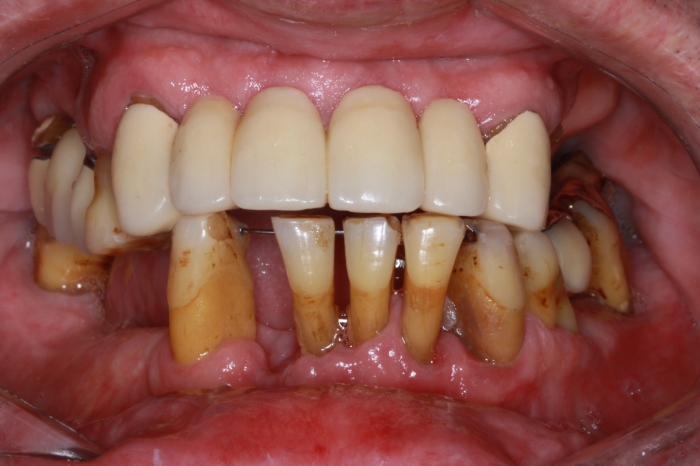

Imagem inicial com vários dentes comprometidos